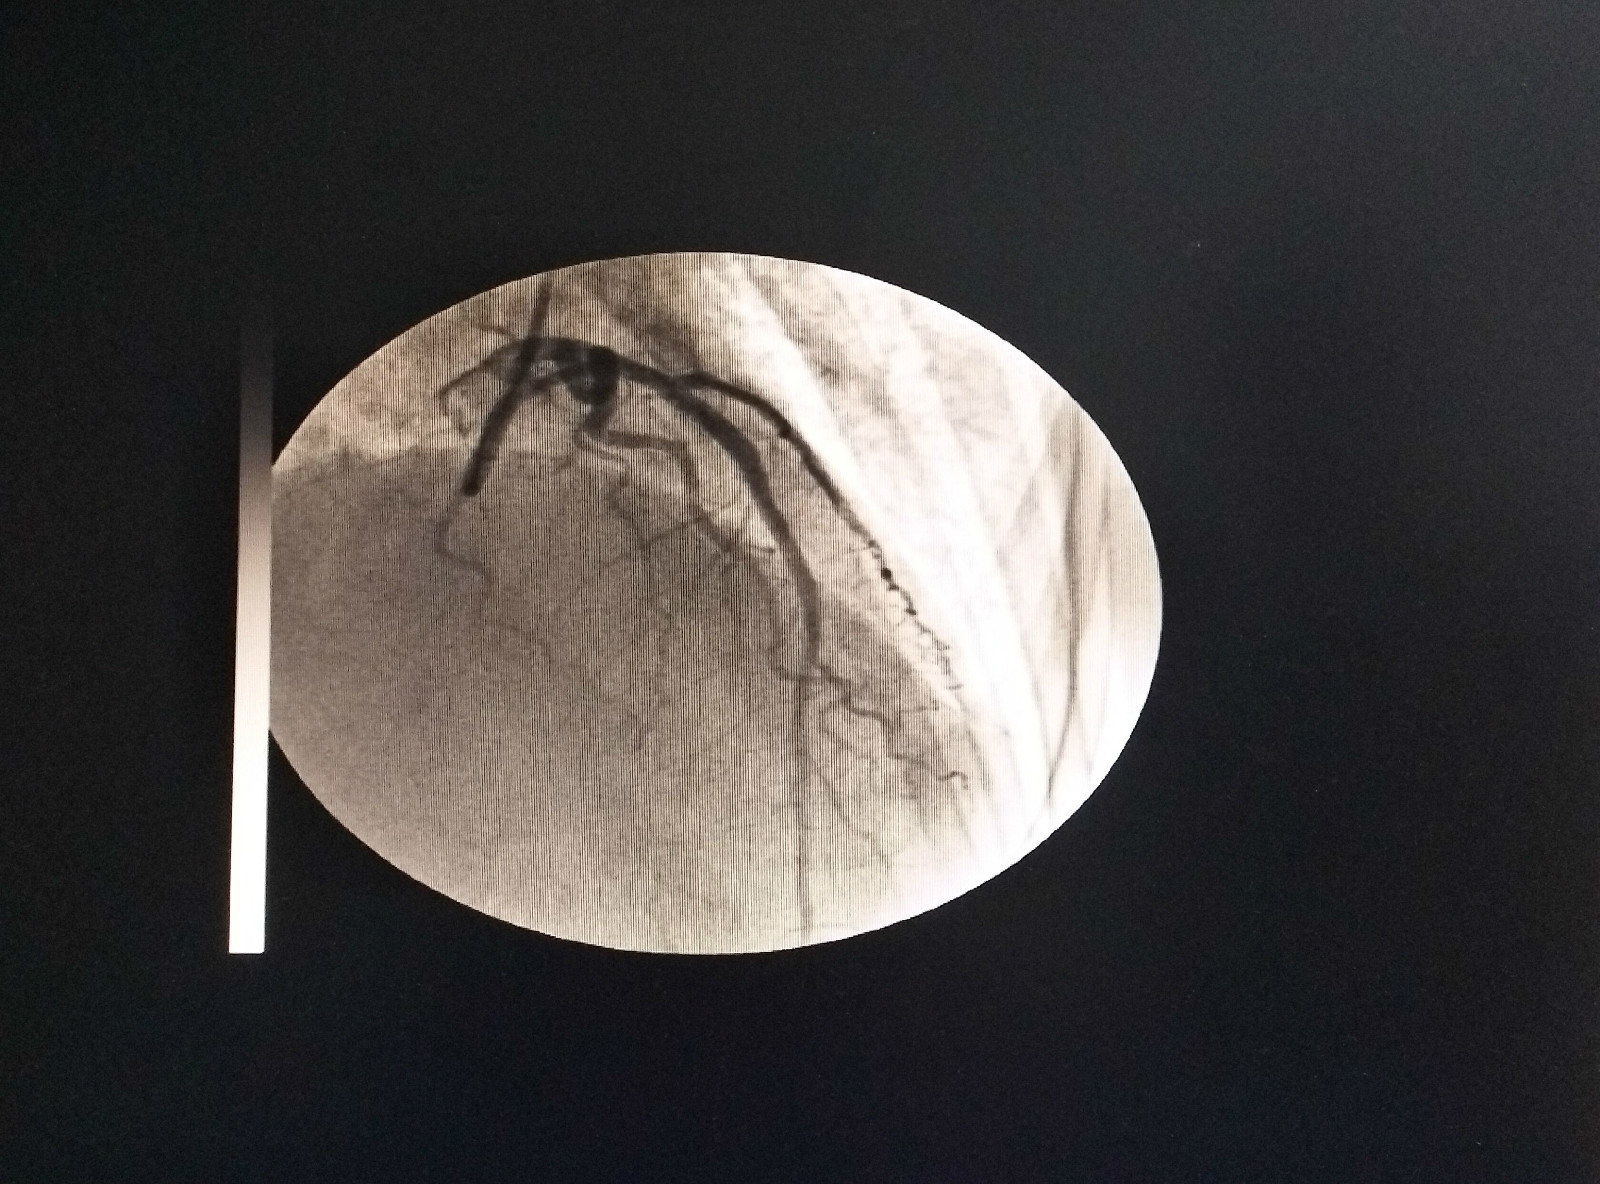

手术后照片(前降支)

冠状动脉造影示前降支中段局限性狭窄约90%